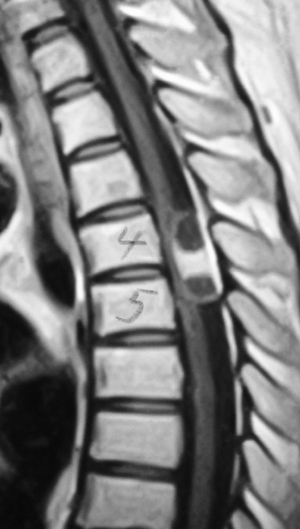

術前 MRI |

術後 MRI | ||